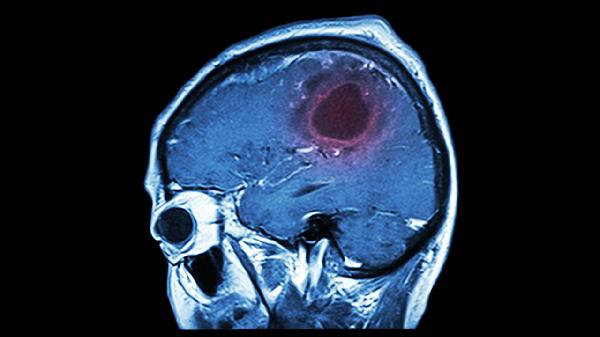

年轻人得脑溢血的原因主要有高血压、脑血管畸形、血液病、外伤、药物滥用等。脑溢血是指非外伤性脑实质内血管破裂引起的出血,起病急骤且危险性高,需及时就医干预。

先天性脑血管发育异常如动静脉畸形、海绵状血管瘤等,血管结构缺陷易在血流冲击下破裂。常见于20-40岁人群,部分患者前期仅有轻微头痛或癫痫发作。通过脑血管造影可明确诊断,需根据病情选择介入栓塞术或显微外科手术切除病灶。

头部受到撞击或穿透伤可直接损伤脑血管,常见于交通事故、运动伤害等情况。外伤性脑出血常合并颅骨骨折,可能出现意识模糊、瞳孔不等大等脑疝征兆。需紧急进行头颅CT检查,严重时需行开颅血肿清除术降低颅内压。